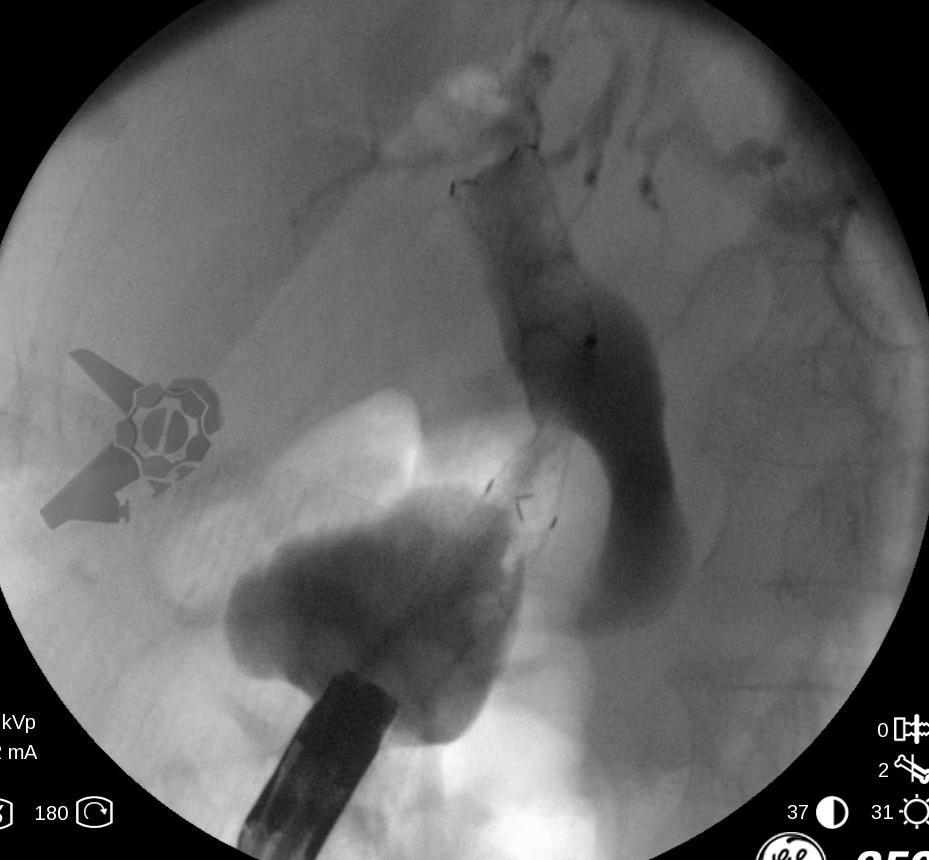

O principal método de drenagem biliar para obstruções malignas distais é a CPRE. Nos casos de impossibilidade/falha, a coledocoduodenostomia ecoguiada (EUS-choledoduodenostomy – CDS) surge como uma das principais opções, porém pode ser desafiadora devido fatores anatômicos, como colédoco < 12 mm, posição do colédoco distante do probe, além da possibilidade de disfunção do stent a longo prazo (1 – 3). Considerando um ducto cístico patente, a drenagem ecoguiada da vesícula (EUS-gallblader drainage – GBD) é uma alternativa interessante, pela técnica em geral mais fácil (alvo/vesícula de maiores proporções). Uma vez que os resultados são bons (100% de sucesso técnico e 10,8% de eventos adversos em um estudo), os autores optaram por investigar estas opções como primeira linha na paliação endoscópica da obstrução maligna distal (4, 5).

Trata-se de um estudo retrospectivo multicêntrico que incluiu casos de EUS-CDS e GBD como tratamento de primeira linha para drenagem biliar (sem tentativa de drenagem por CPRE). Foram incluídos pacientes com ducto cístico patente (avaliação prévia por RNM e/ou TC e durante a ecoendoscopia terapêutica), ambos métodos factíveis no procedimento inicial, colédoco > 12 mm e não candidatos a cirurgia.

Os guidelines atuais recomendam a drenagem ecoguiada ao invés da percutânea para falha da CPRE em casos de obstrução biliar distal maligna (1, 6). A EUS-CDS pode ser tecnicamente desafiadora ou até inviável por uma dilatação biliar discreta e/ou distância do probe para o colédoco. Assim, a EUS-GBD apresenta-se como opção factível quando o ducto cístico é patente e não há histórico de colecistectomia.

Os resultados para os entusiastas das drenagens ecoguiadas são muito positivos: 96% de sucesso técnico, 86% de sucesso clínico e 11% de eventos adversos, todos sem diferença estatística quando comparados a EUS-CDS. Vale lembrar que estudos prévios já nos fornecem evidência para empregar a EUS-CDS no tratamento da estenose biliar maligna distal mesmo sem tentar realizar a CPRE (7). Quando comparada à CDS, a GBD apresenta a vantagem de ser tecnicamente mais fácil, podendo ainda, ser factível com maior frequência.

Outro ponto que deve ser sempre mantido em mente para a GBD é a necessidade de uma boa avaliação da patência do ducto cístico tanto por exame de imagem seccional prévio (RNM e/ou TC) e na ecoendoscopia terapêutica.